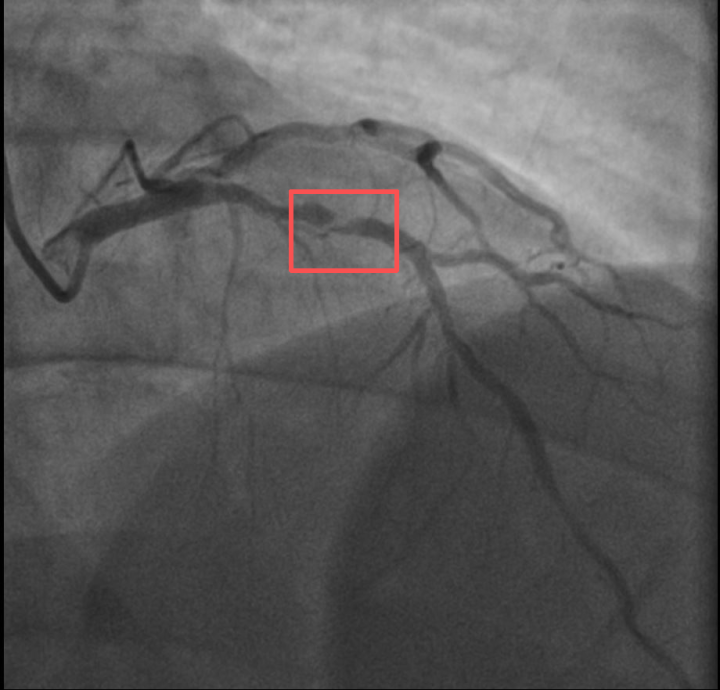

介入治疗前影像图

浙江医院心血管内科的医生分析,剧烈运动导致这位患者心脏的不稳定斑块破裂,进而造成前降支近段次全闭塞。所幸送医及时,孙先生的身体险情被化解。

介入治疗后影像图